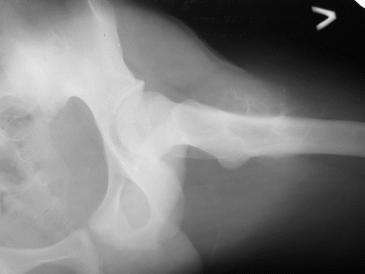

Обратился парень 15ти лет с жалобами на боли в левом коленном суставе. При обследовании обнаружена опухоль в в/з левой бедренной кости.

Проведено КТ заключение( остеохондрома)Подскажите пожалуйста, стоит ли сделать биопсию перед операцией .Кокой операционный доступ и технику операции Вы посоветуете.

Rg

Мне кажется, что это не очень похоже на остеохондрому. Может быть неоссифицированная фиброма? Думаю что перед принятием решения об одномоментной резекции либо о трепанбиопсии стоит более детально уточнить рентгенологический диагноз. Вполне может быть что и тактика изменится на выжидательную. У вас есть более качественные снимки РГ и КТ?

По снимку, хоть и не очень хорошего качества,похожн на кисту, гигантоклеточную опухоль, нельзя исключить саркому Юинга. Важно КТ и клиника.